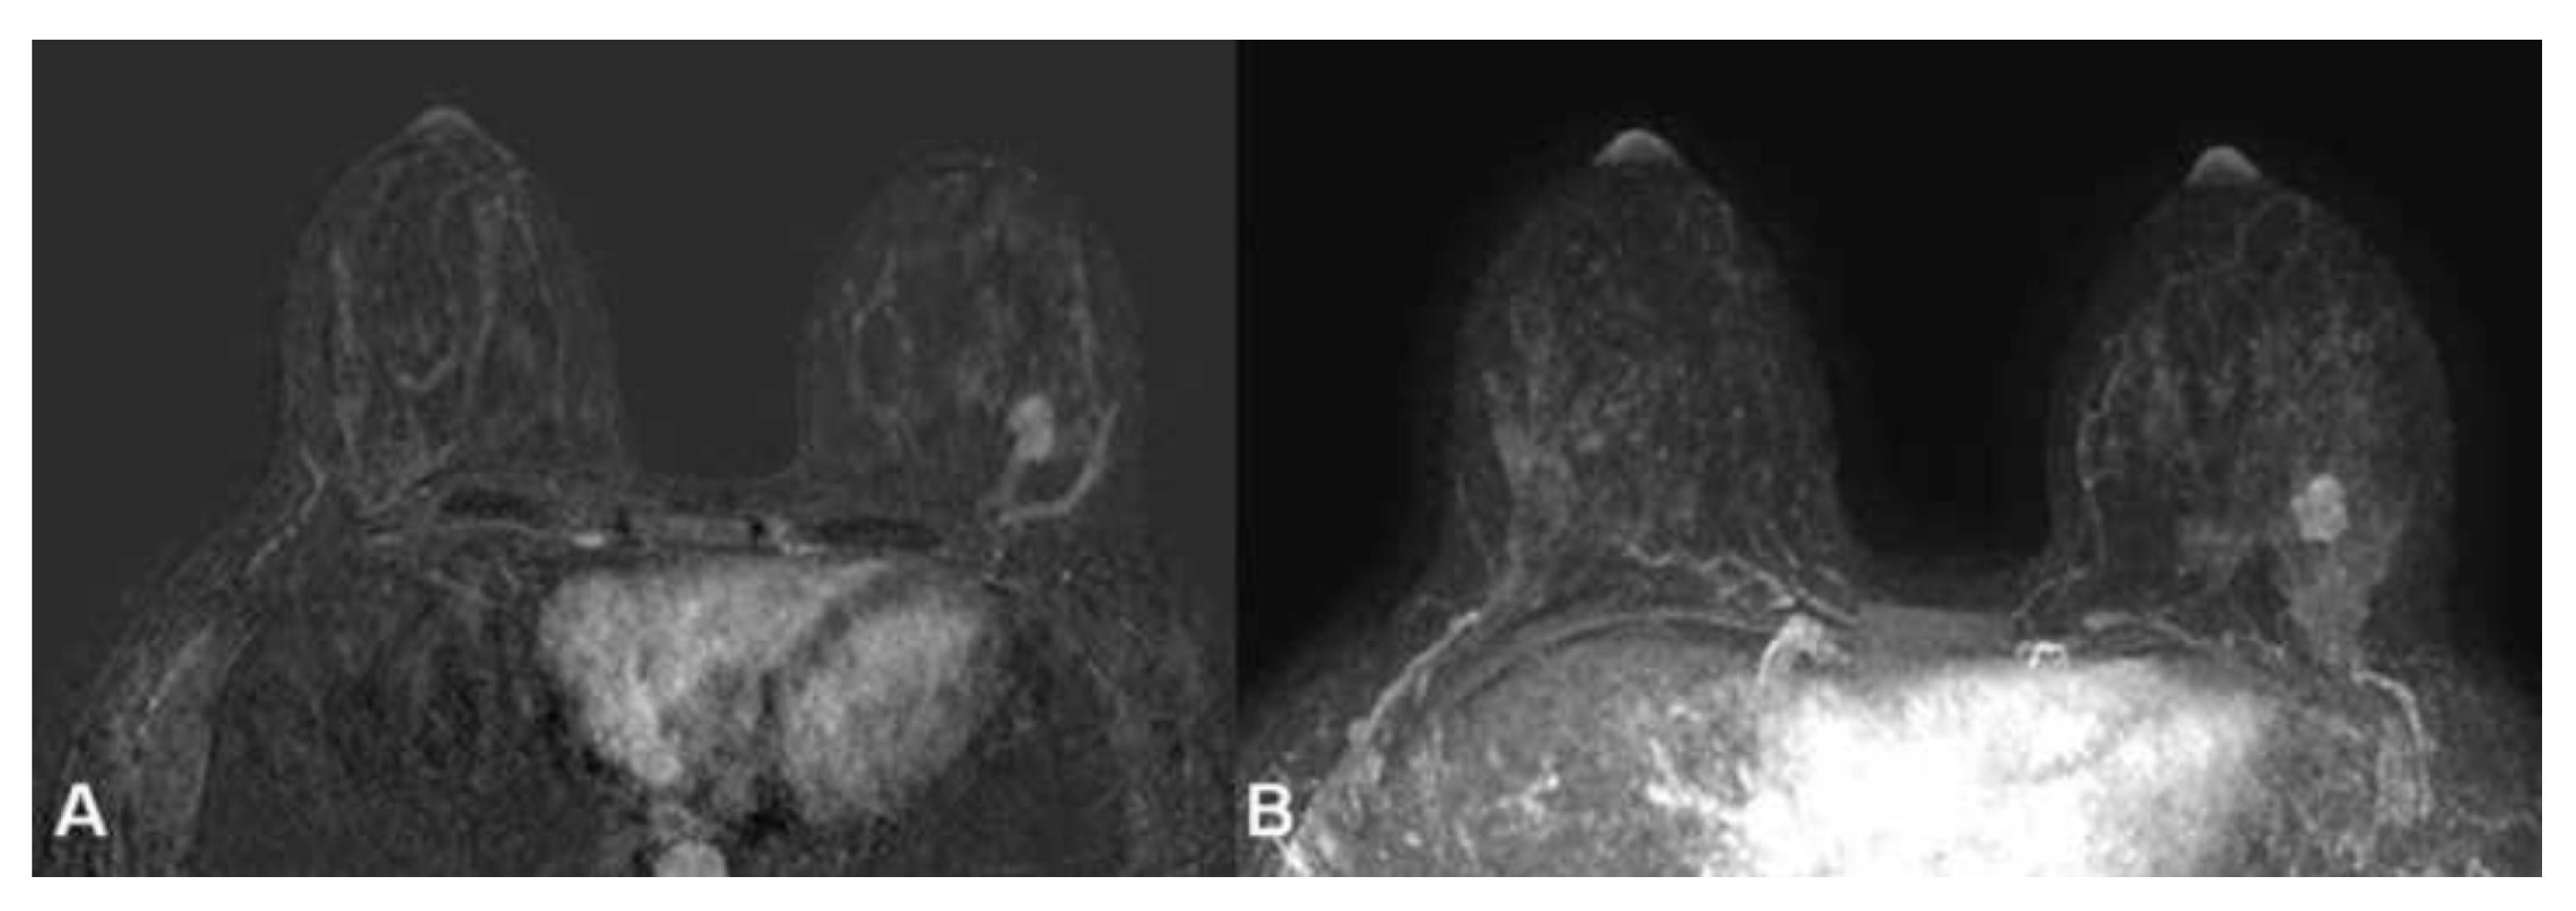

- Background Parenchymal Enhancement (BPE): The degree of normal breast tissue enhancement after gadolinium contrast administration was measured using MRI. BPE was classified into the following four categories: minimal (Type 1), mild (Type 2), moderate (Type 3), and marked (Type 4);

- Breast MRI Findings: MRI was used to evaluate breast tissue characteristics, including BPE and the presence of any abnormal lesions or malignant findings. The MRI sequences included T1-weighted imaging, T2-weighted imaging, dynamic contrast-enhanced imaging, and subtraction imaging for detecting enhancing lesions.

2.2.6. Malignant Lesions Detection